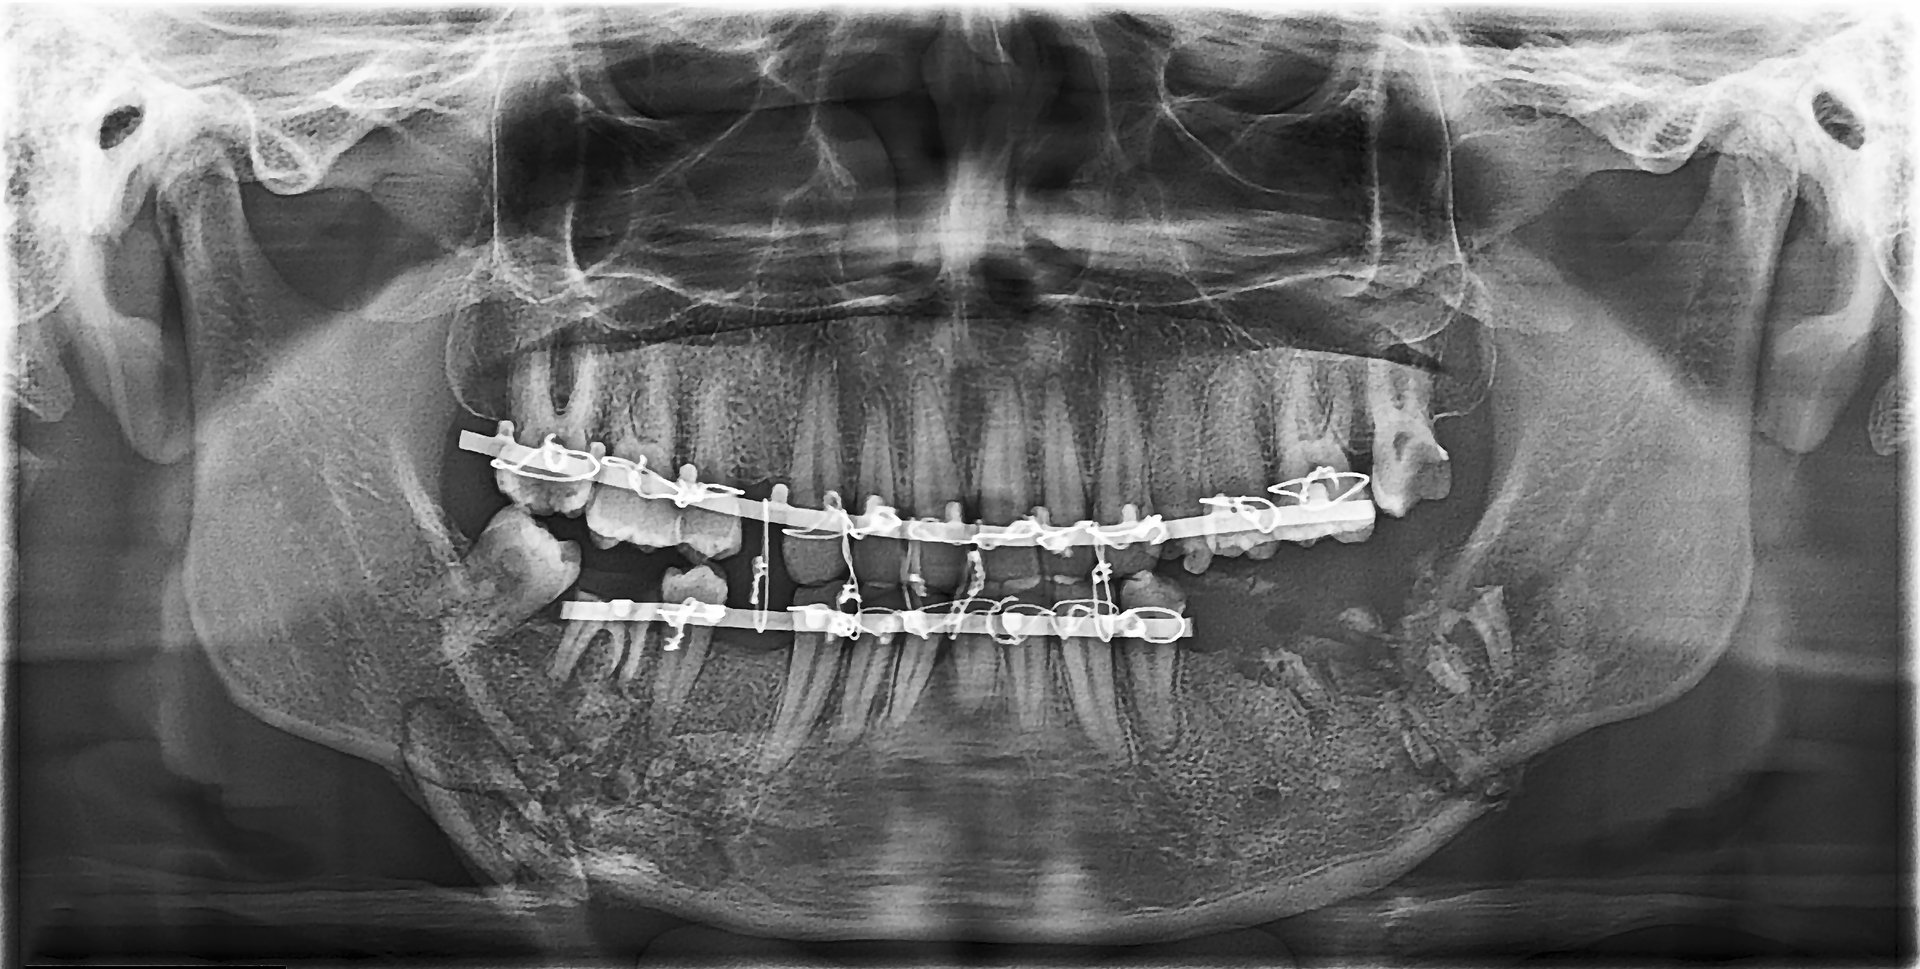

Dental panoramic x-ray showing  bone fracture and fragmentation; the maxillae and the mandible stabilized with a retention arc